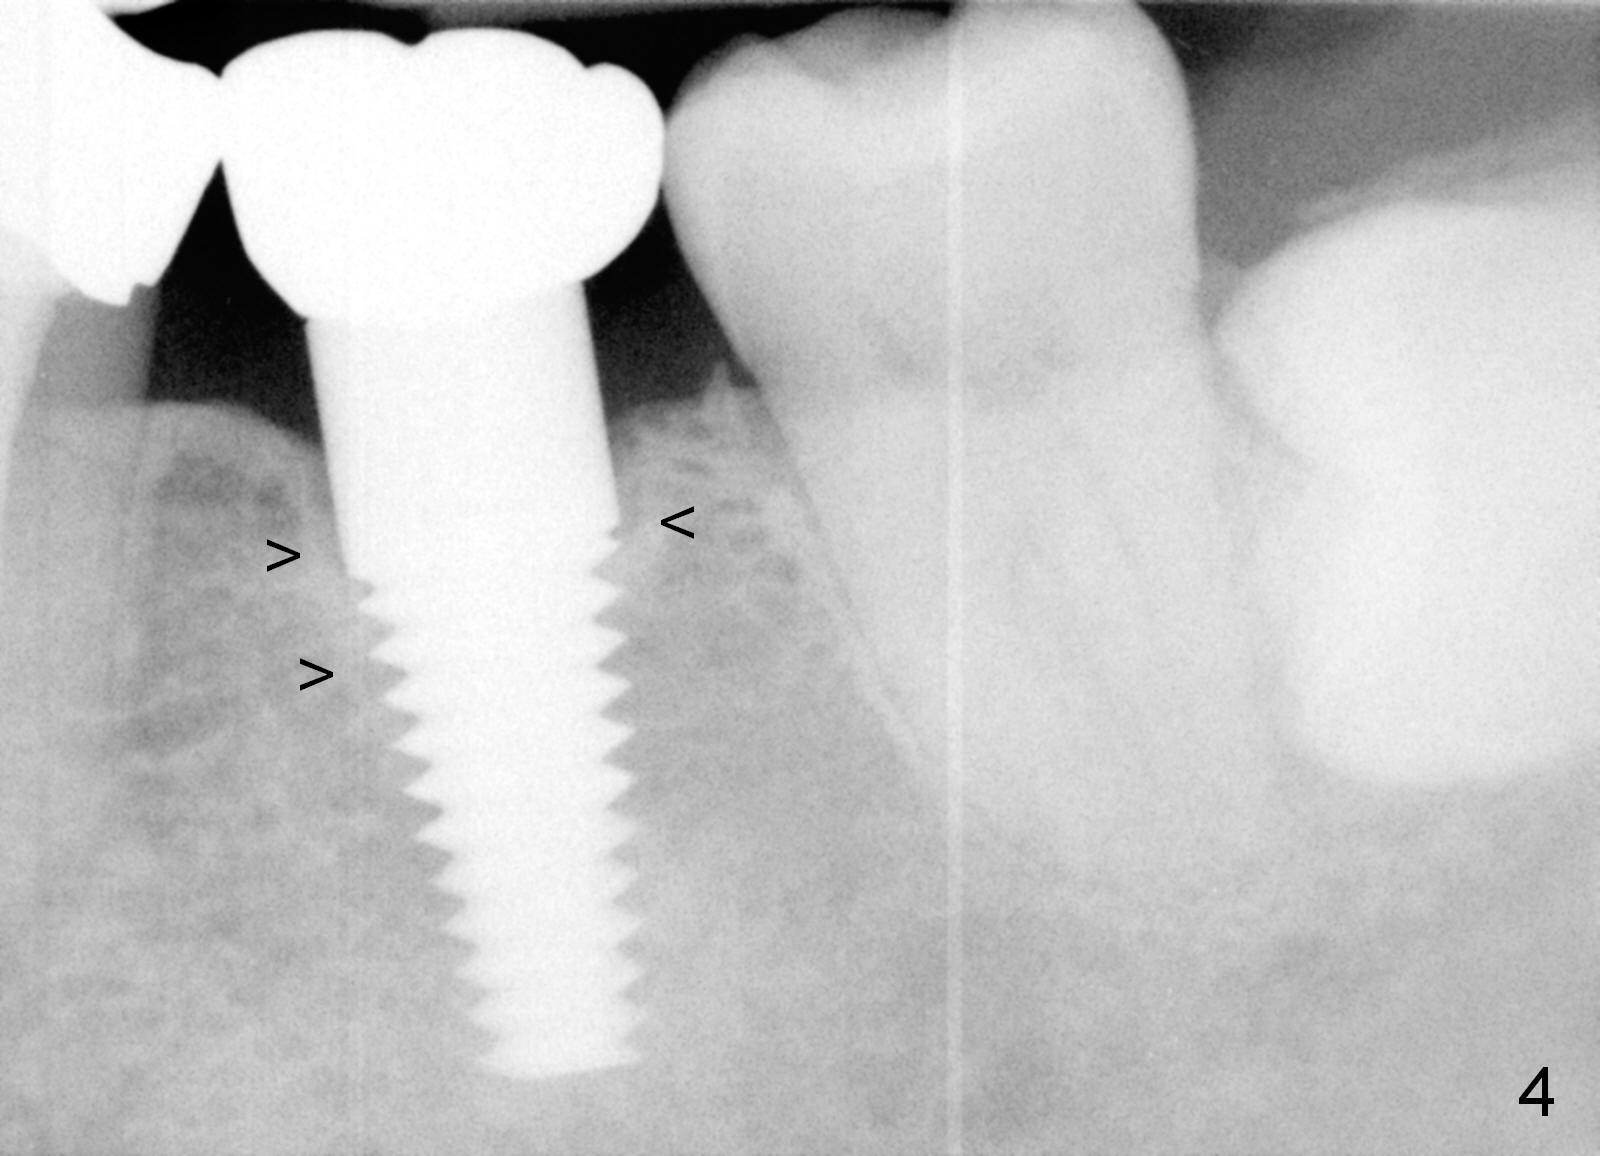

After the challenge is tackled, a definitive restoration is cemented. There is cortical bone formation around the implant 1 year post cementation (3 years postop, Fig.4).